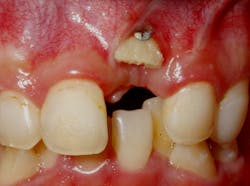

Failures and complications associated with bone augmentation can have a devastating effect on the outcome of dental implant treatment. These complications are classified as either early or late. Early complications include wound dehiscence, membrane and graft exposure, and infection, with the most common complication being wound dehiscence (figures 1a–1c). A strong correlation has been shown between flap tension and wound dehiscence, with wound breakdown occurring in 40% of cases where the flap tension reached 40.1 N as opposed to 10% for flap tensions < 0.1 N.1

Figures 1a–1c: Wound dehiscence occurring after bone augmentation procedures.